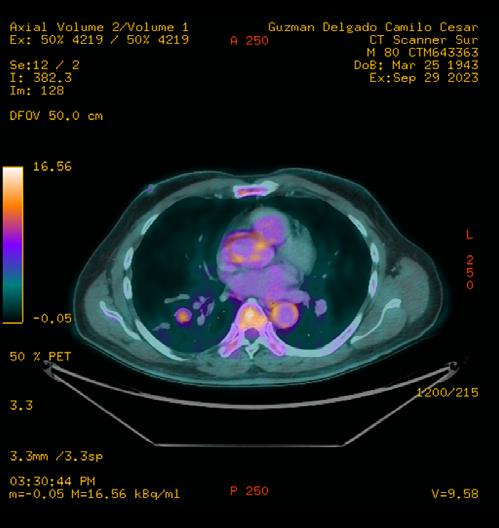

La TC de baja dosis, es la modalidad de imagen más utilizada como método de escrutinio para la detección de lesiones pulmonares, es un estudio rápido, que no requiere preparación previa. ESCANERS DE UN PACIENTE CON

Figura 1-4. Estudio de tomografía simple de tórax, con reconstrucción volumétrica, multiplanares con ventana para pulmón y en mediastino (, en donde se observa el nódulo pulmonar sólido de bordes lobulados hipodensos.

Se le realiza estudio de tomografía simple de tórax en donde se encontró en el segmento anterior del lóbulo inferior derecho nódulo sólido, con diámetro de 22mm, volumen de 2.9ml, condiciona disminución del bronquio segmentario, con secreciones endoluminales distales, de acuerdo a la clasificación de LUNG RADS con categoría 4B, alta sospecha de malignidad. Sin evidencia de lesiones nodulares en el resto del parénquima.

Posteriormente, se realiza estudio de PET-CT con 18FDG , con hallazgos de metabolismo asociado y SULmax de 2.0, se recomienda realizar biopsia.

Figura 5. Estudio de PET-CT con FDG que muestra hipercaptación del radiofármaco en el nódulo pulmonar, lo que traduce en metabolismo aumentado.